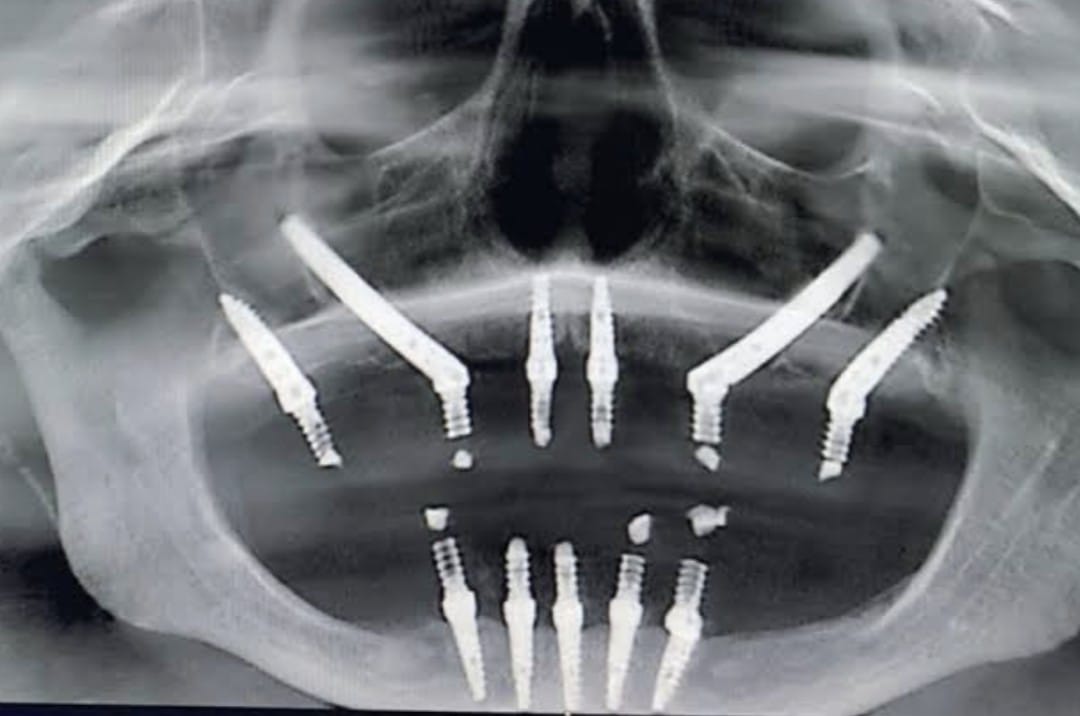

Prosthodontics is a specialized branch of dentistry that focuses on the restoration and replacement of missing or damaged teeth. It plays an important role in improving oral function, appearance, and overall quality of life. Teeth can be lost or affected due to decay, trauma, or age-related factors, and prosthodontic treatments help restore a natural and confident smile.

Abhi K"I had an accident few years back and was seriously injured and i lost seven of my teeth and because of that i was facing a lot of difficulties . I was not even able to chew food properly. Then i came to know about dr. Philip from J P dental clinic who is also a dental surgeon in mission hospital. I consulted him nearly a month ago and he fixed all my problems. I felt so safe and secure in his care . Im so grateful to dr. Philip sir and jp dental for bringing my smile back."